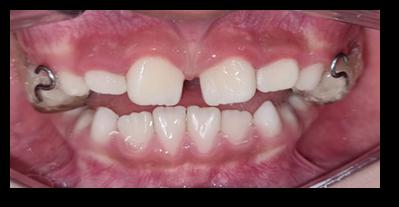

Se aplica un proceso de arbitraje en pares doble ciego de forma anónima, objetiva, consistente y con crítica constructiva. Los árbitros no tienen ningún vínculo de tipo laboral, académico o personal con los autores.

Todo manuscrito que no se adecúe a estos principios y se compruebe una mala práctica será eliminado o retractado, en función del estado en que se encuentre en el momento de detectar faltas éticas.

1. Carpio-Deheza G. Manual de instrucciones para la presentación de protocolos y monografías de diplomados, protocolos y tesis de espcialidad clínica/ quirúrgica, tesis de maestrías y doctorados en salud. Cochabamba: Universidad Mayor de San Simon, Facultad de Medicina Dr. Aurelio Melean, post grado UMSS; 2019.

2. Patrias K. Citing Medicine; The NLM Style Guide for Authors, Editors, and Publishers. [Online].: Bethesda (MD): National Library of Medicine (US); 2007 [cited 2022 marzo 29. Available from: https://www.ncbi.nlm.nih.gov/books/NBK7256/.